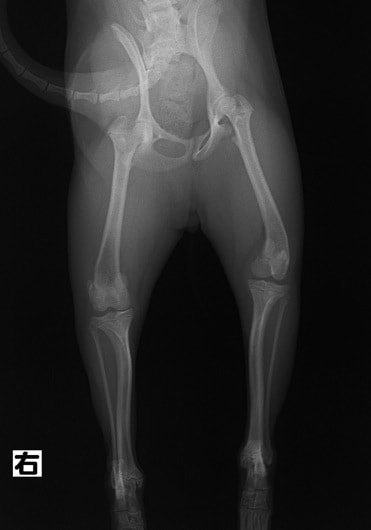

■ 症例24 キャバリア 7か月

左右膝蓋骨内方脱臼(左:グレードⅣ 右:グレードⅢ)

以前から左右後肢の跛行が認められ、整形外科学的検査・レントゲン検査により左右の膝蓋骨脱臼が認められた。症状が重度である左膝の膝蓋骨脱臼整復術を行った。外科手技は縫工筋及び内側広筋の解放、脛骨粗面の外側転位、滑車ブロック形造溝術、内外側関節方の縫縮を実施した。術後一か月時点で、左の膝蓋骨は安定しており経過は良好である。

本症例は成長期における重度の膝蓋骨脱臼であり、術後の再発の可能性もあるため、経過をしっかりと観察していく必要がある。また、今回手術を実施していない右膝に関しても経過を観察し、手術を検討していくこととする。